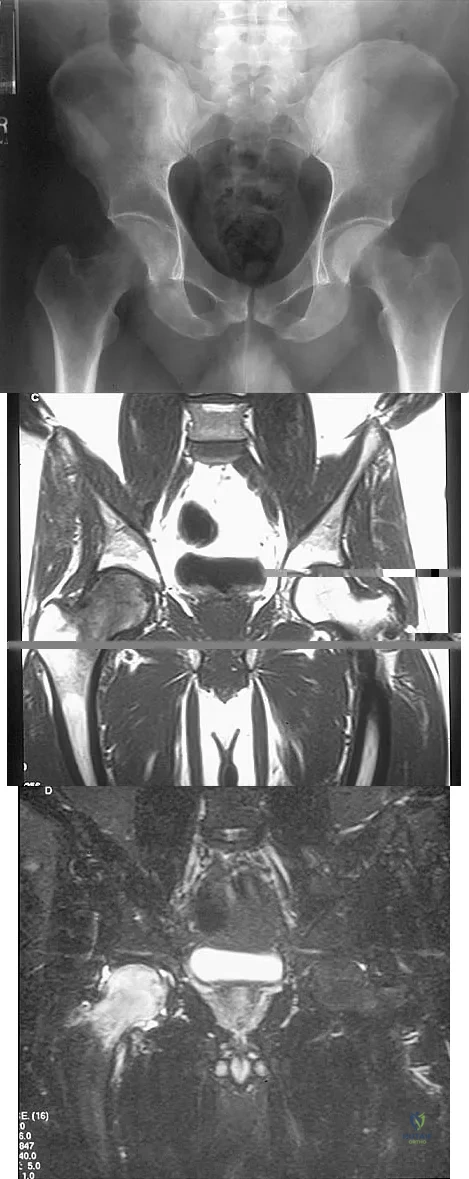

An AP radiograph of the pelvis is shown in Figure 4. What muscle attaches to the avulsed fragment of bone identified by the arrow?

Figures 10a through 10c show the plain radiograph and MRI scans of a 41-year-old man who has right hip pain. What is the most likely diagnosis?